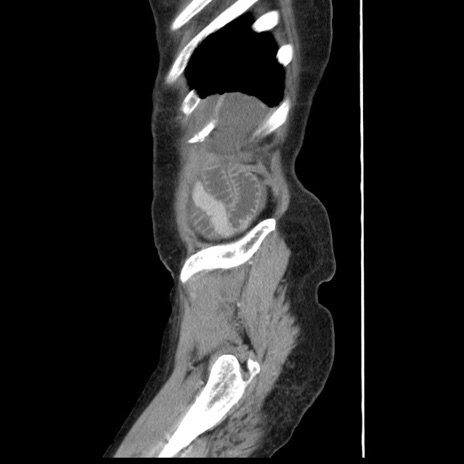

症例1(矢状断像)

【症例】80歳代女性

【主訴】腹痛

【現病歴】8時間前から腹痛あり来院。

【既往歴】糖尿病、脂質異常症、子宮体癌にて子宮全摘術

【身体所見】意識清明・会話良好だが腹痛で苦悶様、全腹部にわたって反跳痛と圧痛あり

【データ】WBC 13600、CRP 0.14、LDH 224、CK 90